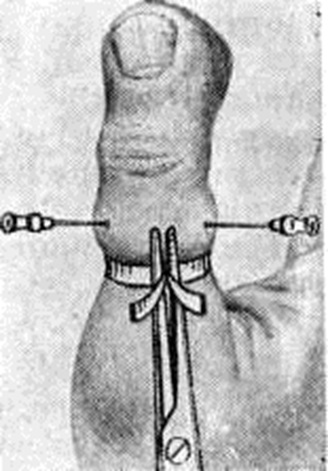

В стадии гнойно-некротического воспаления (не позже первой бессонной ночи) необходима операция, при которой осуществляют широкое вскрытие гнойного очага, радикальное иссечение некротизированных тканей (смотри полный свод знаний: Некрэктомия) и рациональное дренирование (смотри полный свод знаний). Операцию производят обычно под местным обезболиванием по Лукашевичу— Оберсту (смотри полный свод знаний: Анестезия местная) с наложением на основание пальца тонкого резинового жгута с целью гемостаза (рисунок 8). При Панариций проксимальной фаланги или переходе воспалительного процесса на кисть прибегают к внутривенной или внутрикостной анестезии, а чаще к общему обезболиванию (смотри полный свод знаний).